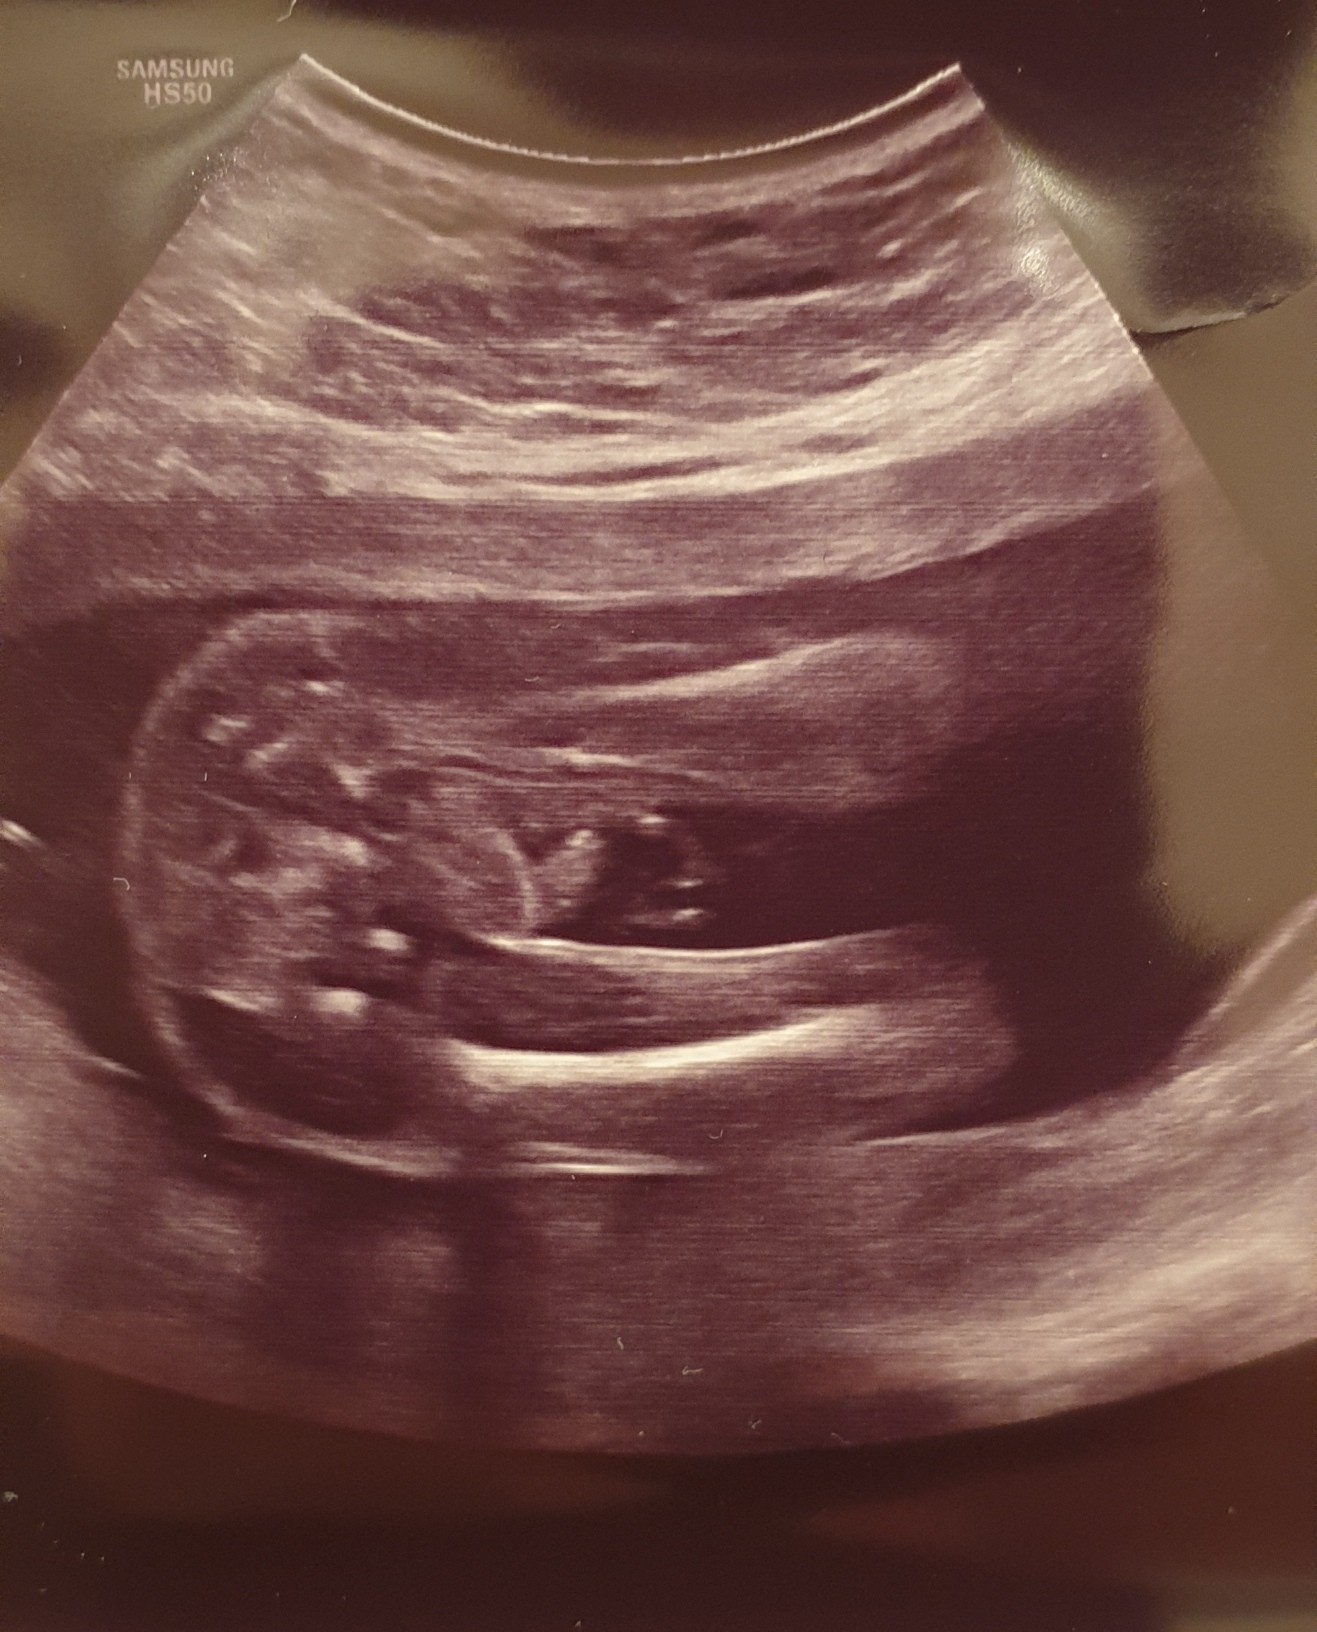

Pewnie dziewczynka.Bo wśród moich znajomych to właśnie córeczki długo się ukrywały i zazwyczaj były mniejszeJa po polowkowym. Dziecko młodsze o 1,5tyg wcześniej różnica była 2dni. Położenie miednicowe i dalej nie wiem czy chłop czy baba.

Czyli z tym młodszym jak u mnie.Ja po polowkowym. Dziecko młodsze o 1,5tyg wcześniej różnica była 2dni. Położenie miednicowe i dalej nie wiem czy chłop czy baba.